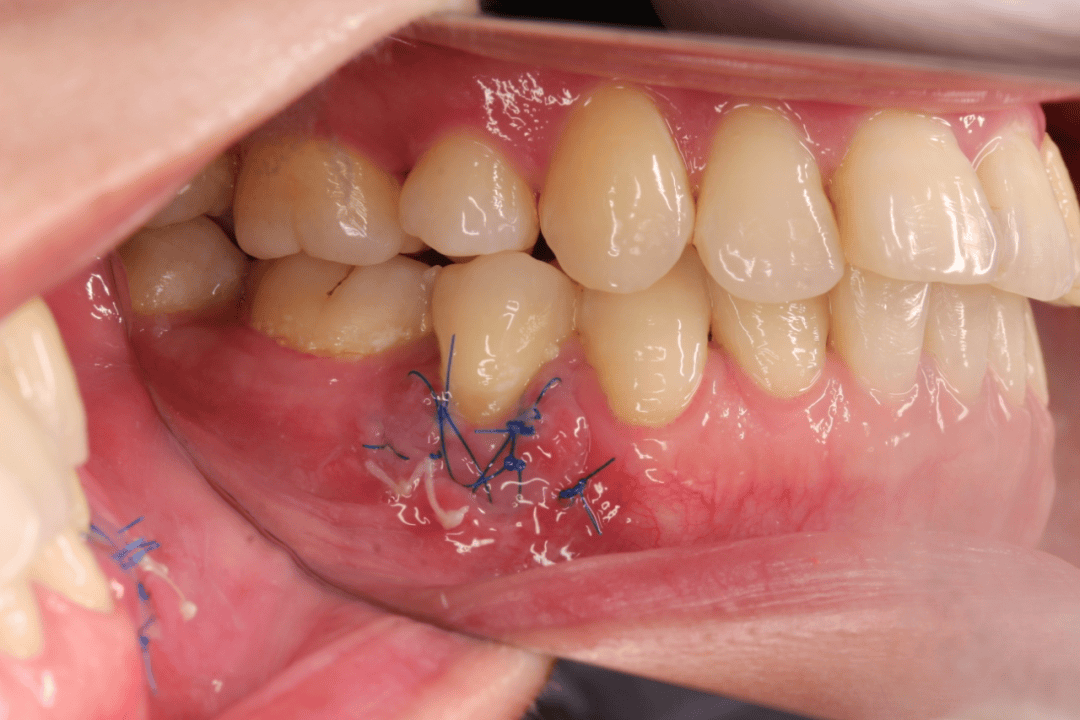

3. 严重萎缩?试试牙周手术

如果牙龈萎缩严重,比如牙根暴露太多、牙缝过大,单纯的基础治疗可能不够,医生会建议做牙周手术,比如 “游离龈移植术”—— 从口腔其他部位取一小块健康的牙龈,移植到萎缩的区域,覆盖暴露的牙根,改善外观和功能。

术前 术中 术后